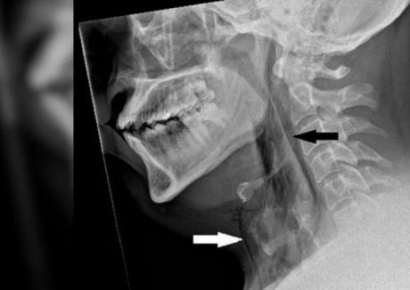

재채기할 때 코와 입을 막고 참으려고 하면 재채기를 내뱉을 때보다 상기도의 압력이 20배 이상 높아져 위험하다는 경고가 나왔다. 21일 미국 과학 전문 매체 라이브사이언스는 재채기를 참았다가 기도가 파열된 남성의 사례를 보도했다. 영국 30대 남성 A씨는 목이 부어 움직이기 힘든 상태로 병원 응급실을 찾았다. 앞서 A씨는 운전을 하다가 꽃가루 알레르기 증상으로 재채기가 나오려 하자 코를 쥐고 입을 다물어 재채기를 참